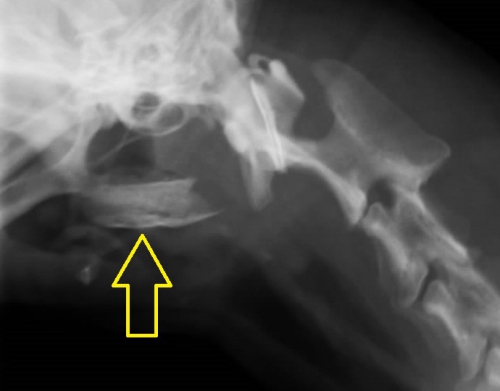

”ジャーキーを食べた直後”ということと、診察室での様子からやはり食道の異物が疑い、頸部のレントゲン検査に加えて、確定診断のためにバリウムによる食道造影を実施したのが下写真です。

頸部レントゲンで、「異物が存在する」はずの黄色の丸で囲んだエリアには異常は認められません。

ここでバリウム造影検査を行ったものが下写真です。上の写真黄色のサークル内でほぼ見えない異物が造影剤で浮かび上がっているのがお分かりだと思います。異物は咽頭のすぐ下から食道に入って数センチ以内の場所に存在しているようです。